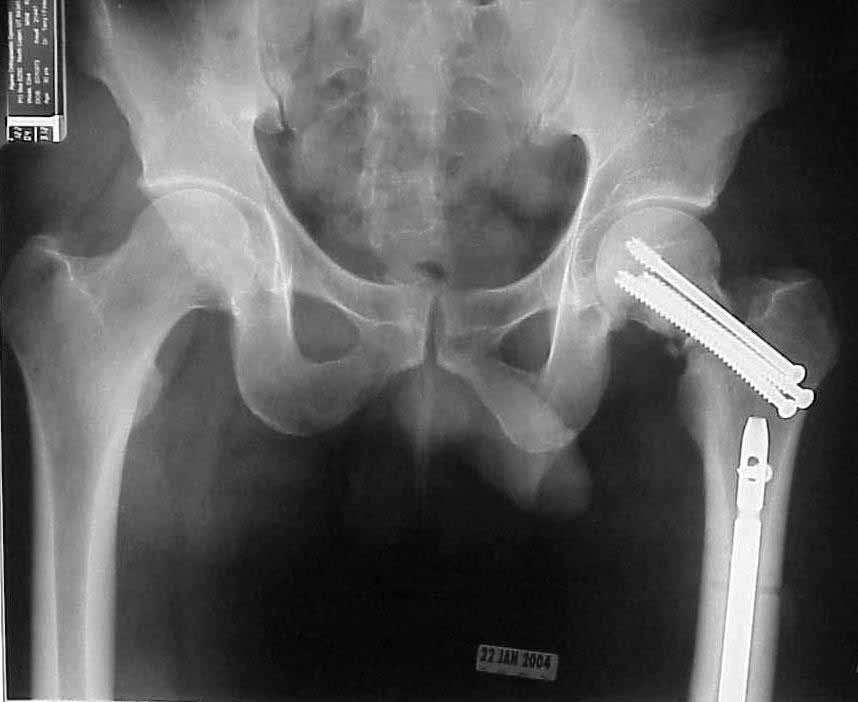

30 y/o man in head-on MVA 12/22/03 sustaining grade II open left femoral midshaft fracture (treated with appropriate staged debridement and retrograde statically locked IM nail), left lateral split tibial plateau fracture (treated with reduction and percutaneous cannulated screw fixation) and comminuted left femoral neck fracture (treated with open reduction and non-compression screw fixation). All initial treatment at another institution and patient recently came to me for follow-up care (he was travelling out of town when he was injured). He has a large (7cm) defect of lateral half of femoral shaft fracture which I plan to pack with a ton of bone graft next week (open fracture site soft tissues healed nicely without sign of infection).

What about the femoral neck? It's shortened, the head is inferiorly translated and I think probably in a little varus (hard to measure neck/shaft angle without a neck). However, I'm not sure I can improve the alignment given the significant bone loss, probable difficulty with repeat fixation once the current screws are removed and bone graft would almost certainly end up in the joint (no cortex to contain it). My inclination is to get the shaft to heal, try a bone stim on the neck and prepare bone stock for THA if/when neck doesn't heal, but I'm open to ideas from those more enlightened and/or optimistic than I am.

Only small part of femoral shaft fracture visible on one xray. I would be interested in seeing xrays of the shaft fracture. I would be hesitant about bone grafting the femoral shaft fracture early. It might heal. Femoral neck fracture is going to be a problem. I agree, in varus and almost appears with some distraction at the fracture site. I do not think anything now will significantly increase the chance of salvage. I would suggest observation over a reasonable period of time while on crutches, documentation of healing or lack of healing with CT or tomogram (hard to get as the machines are fewer and fewer), then definitive treatment of what is left at the hip. Not an agressive approach but one that gives a 30 year old a chance to heal given how he was initially treated.

Speak to the initial surgeon. How did the shaft traumatic wound and local defect appear? How much associated soft tissue injury? What interval did they use for the femoral neck procedure? What did the surgeon tell you was found at operation? How much bone was removed? What was the capsular condition within the surgical interval? How did they handle that? Other surgical details? The neck is currently malreduced, but what did the initial postop films show? Was it ever reduced?

In a young active adult, very few would criticize you for a repeated attempt at an accurate reduction and stable fixation. Assuming all answers to the above questions are satisfactory, we'd strongly consider either repeat reduction and fixation....or more likely proximal femoral osteotomy for reorientation of the fracture line and blade plate fixation for support. Reinhold Ganz once used the analogy of "supporting a rotten tomato with strong, firm hands" for such a clinical scenario. Make some drawings and see what they look like with osteotomy and blade fixation...you may be surprised.

It looks like the films are one month into treatment. It is hard to think that the hip will do well as it is. I also don't see how it is going to reduce accurately anymore, as it appears some bone may be absent.

I don't know if you think a Pauwels-type valgus-producing osteotomy seems overly aggressive, but it has much to offer. It would give you better alignment, better length, and possibly a better likliehood of union. A blade would address the fixation problem, and the operation does not burn bridges.

Therefore, the images sent seem to indicate bone loss from comminution, correct?, and the alignment abnormality is from a rotational malposition of the neck, as well as the impaction-comminution seen at the basi-cervical-transcervical level.

I would strongly vote for revision ORIF-Watson Jones approach, formal capsulotomy-reduction of the malrotation-impaction-&-bonegrafting of the neck. It may require inferior neck plating as described years ago by Professor Marti (Springer Verlag publishers). With the present day added advantages of ortho-biologics (AGF/IgF aka Symphony, these may hedge the bets as it were. Even if a prior open reduction was indeed performed, my preference is still for the direct repair approach. Phil Kregor has given some excellent talks on femoral fixation with great illustrations as well.